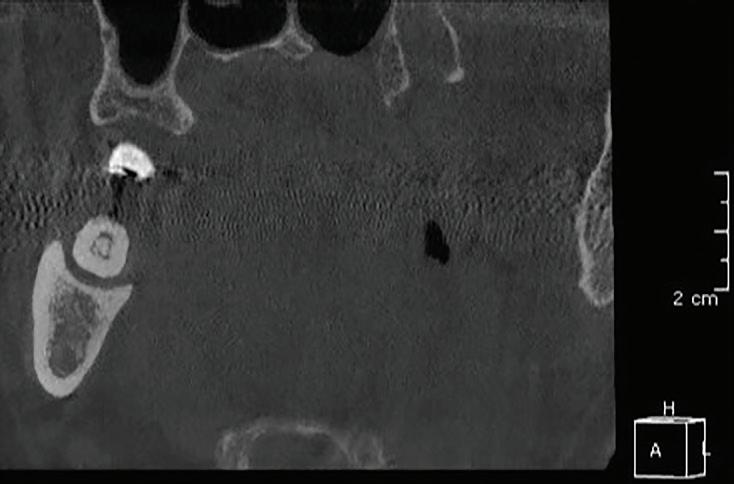

After tooth extraction and socket preservation, patients heal for at least 3 to 4 months. Once the healing process is complete, among the most important procedures for implant planning are cone beam computed tomographic (CBCT) and intraoral scans. The CBCT scan is a 3-dimensional (3D) radiograph that shows the patient’s bone in ways that cannot be seen on 2-dimensional images such as periapical, bitewing, or panoramic radiographs. The use of CBCT scans for implant cases is becoming common because of the important information provided, including bone height, bone width, and the location of arteries, veins, nerves, and other important anatomical features.2

In addition, CBCT images can be used to assess bone density. Bone density ranges from D1 to D4.3 The density is measured in a ratio of cortical-to-cancellous bone. Cortical bone, which makes

up the outer portion of the bone, is dense and has low vascularity. Cancellous bone, which makes up the inner portion of the bone, is not dense and has higher vascularity. D1 bone consists of a high percentage of highly dense cortical bone and minimal to no cancellous bone. D4 bone has a high percentage of low-density cancellous bone and little to no cortical bone. In bone that is more cortical and more dense, the clinician will generally make a larger osteotomy to reduce the stress put on the dense bone. In bone that is less dense and more trabecular, the clinician can make a more undersized osteotomy to ensure good primary stability of the implant. Depending on the type and density of bone found on the preoperative CBCT, the clinician can modify the implant placement technique to adjust for the findings. In my experience, the density of grafted sites is usually classified as D2, but this can vary depending on the type of graft used (Fig 1 and 2).

Fig 1. CBCT images confirm healing of the extraction site after grafting. Fig 2. An occlusal CBCT view reveals the density of the healed graft.